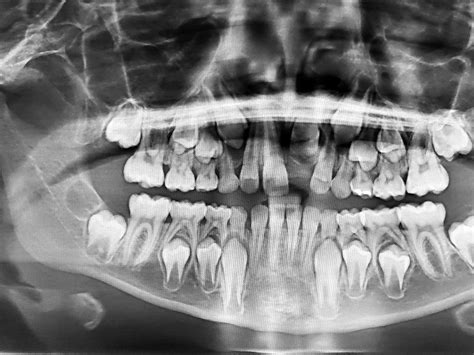

Después de 25 años de actividad profesional, continuamos viendo la cara de impacto y sorpresa de los padres cuando ven una primera radiografía de la boca de sus hijos. ¿Pero cuántos dientes hay en la boca? Suele ser lo primero que preguntan. Y es que en la boca de un niño podemos llegar a ver una auténtica multitud, entre los dientes de leche que ya tienen y los definitivos que se están formando y esperan a salir, en el sitio que ocupan los primeros.

Es lo que ocurrió en el caso de Melisa que llegó a la consulta con seis años. No le habían salido los dientes definitivos correspondientes a esa edad, que son los centrales, los laterales inferiores y la muela de los 6 años. A la primera radiografía vimos el problema. En su boca estaban los 16 dientes de leche, ya había perdido los incisivos temporales inferiores, 10 arriba y 6 abajo.

Y creciendo en sus encías para sustituirlos estaban ya los definitivos que suelen ser 32 dientes (8 incisivos, 4 caninos, 8 premolares y 12 molares que incluyen las 4 muelas del juicio que no siempre acaban saliendo en la mayoría de casos por falta de espacio). Con esta primera imagen ya veíamos la dificultad que tendrían los laterales superiores para salir debido a la falta de espacio y deducimos que en un futuro podría tener problemas de dientes impactados en los caninos. Además lo que sí era ya una certeza era que había una clara transposición de dientes.

La raíz de uno de los premolares definitivos se había cruzado en el camino del canino. Esto estaba ocurriendo porque Melisa tenía un problema transversal de falta de espacio en su la boca. Así que el primer paso fue ensanchar su boca, demasiado pequeña, con uno aparato ortopédico, un disyuntor superior y un Lip Bumper inferior, cogido a los molares temporales. Así conseguimos crear más espacio donde no lo había. Pasó el tiempo, le hicimos un nuevo control con una radiografía y este era el nuevo estado de su boca.

En esta segunda radiografía ya sumamos al diagnóstico de trasposición el de dientes impactados. Los caninos, tanto los superiores como los inferiores, estaban cruzados y no se habían enderezado para salir, además la raíz del premolar estaba cruzada por delante del canino. Decidimos actuar de inmediato con unas extracciones seriadas de dientes de leche, que realizó el cirujano Alfonso Borja, para ser nosotros y no el caos en su boca, los que dirigiéramos la erupción de los dientes permanentes.

Las radiografías de un niño de 6 años, la primera vez que las ves, dan un poco de miedo, porque puedes ver los dientes de leche y todas las definitivas escondidas debajo. En este artículo, repasaremos los tipos de movimientos que solemos ver en las radiografías y que, gracias a ellas, nos permiten realizar movimientos con tiempo suficiente para evitar males mayores.

Y en esta última, el colmillo se ha ido hacia atrás y está posicionado entre los dos premolares. En esta radiografía sale una pala extra, que deberá quitarse. Cada diente de leche es “empujado” por su diente correspondiente definitivo. En este paciente encontramos que le faltan los dos incisivos laterales y nunca le saldrán. En este otro caso, vemos que este diente de leche nunca tendrá un definitivo, algo que se llama agenesia.